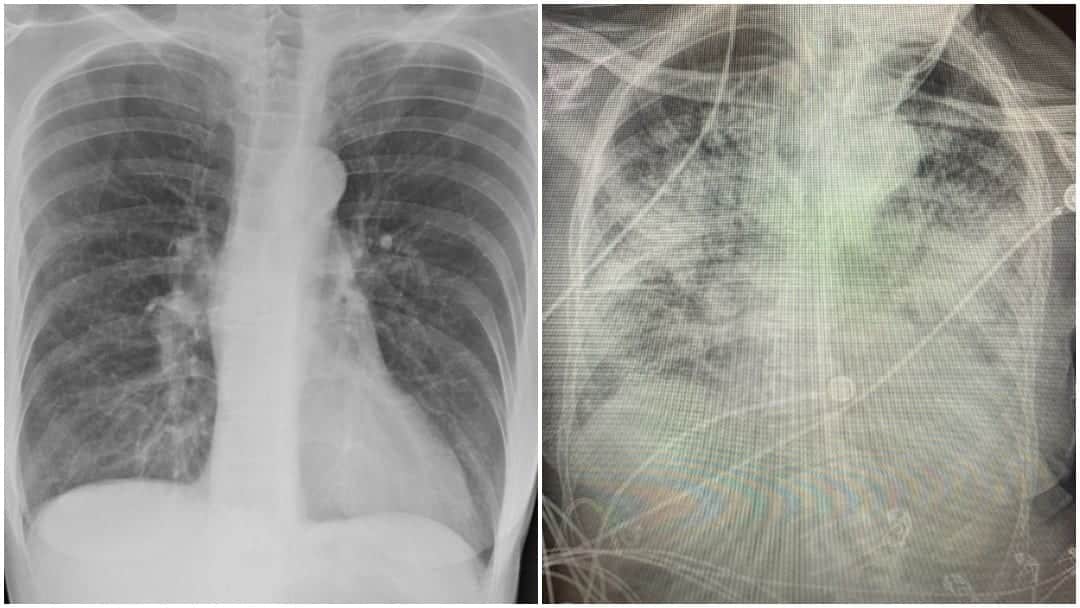

A su vez, recordó que existe evidencia científica «sólida» que demuestra una asociación «peligrosa» entre Covid-19 y tabaco y que la exposición a los tóxicos del tabaco se relaciona con «presentaciones más graves y con un peor desenlace de esta enfermedad», hasta el punto de que la presencia de una historia de tabaquismo aumenta en un 79% las posibilidades de necesitar ingreso en UCI o de morirse y en un 96%, de desarrollar Covid-19 grave.